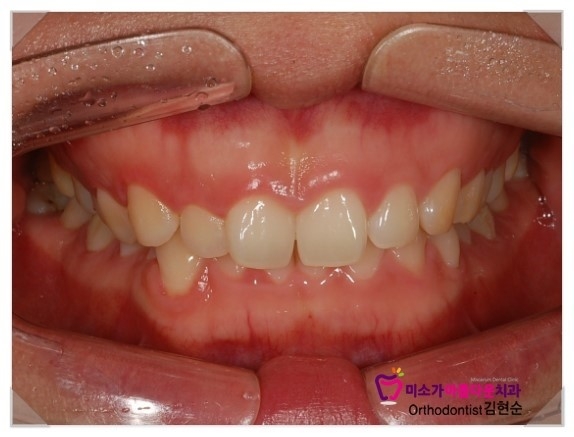

치아교정을 생각하면 돌출입이나 덧니 이 두가지를 생각하시는 분들이 많은데

그 외에도 교정을 많이 받는 또 다른 사례자가 바로

과개교합(deep bite)입니다.

윗니만 보이거나 아랫니만 보이는 것으로

심미적으로 상당히 좋지 않아서 이런 경우엔 대부분 교정을 선택하게 됩니다.

아랫니가 거의 없는 것 같아서 너무 고민이라고

하셔서 이번에 교정으로 치열이 다시 정렬이 끝난 사진입니다.